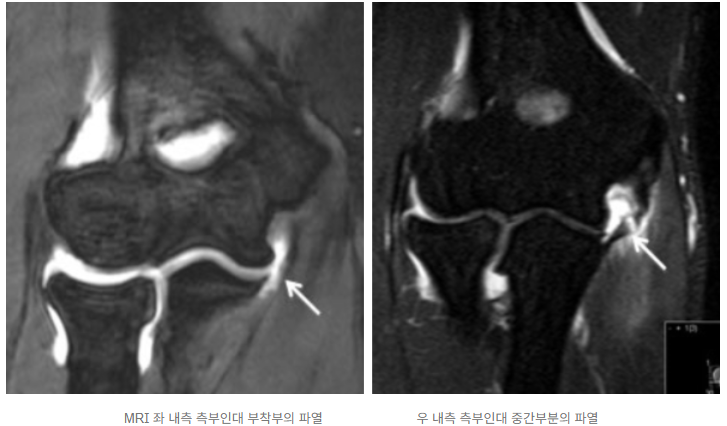

영상 촬영(X-ray, 초음파, MRI): X-ray로 뼈의 석회화, 성장판 손상 등을 확인하고, 초음파로 힘줄과 인대 손상 여부를 빠르게 파악할 수 있습니다. 필요한 경우 MRI로 미세 손상이나 조직 변화를 정밀하게 진단합니다.